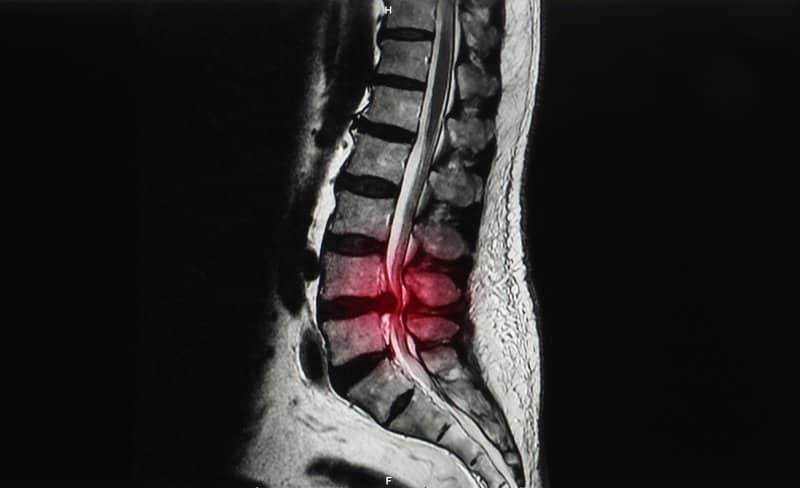

As this is a more serious type of disc herniation, treatment should be discussed with a medical professional. They will provide a physical examination as well as any medical imaging like an MRI (Magnetic Resonance Imaging) that will help determine the extent of your injury.